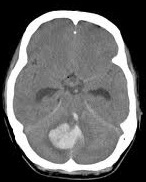

• Brain Abscess

• Brain CT Collection

• Cerebellar Haemorrhage